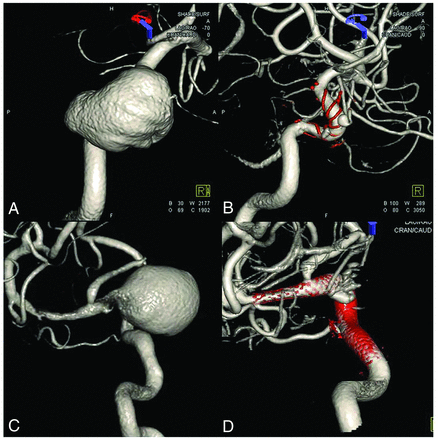

In-stent balloon angioplasty is performed when the stent-to-wall apposition is poor or stenosis is evident in the parent artery because either condition greatly increases the risk of thromboembolic events and subsequent parent artery occlusion.18,28,29 In addition, high-velocity blood flow into the aneurysm caused by stenosis of the proximal parent artery compromises the effect of FD and might induce delayed aneurysm rupture (Fig 3).20,30,31 However, we found that patients who underwent in-stent balloon angioplasty are more likely to be in the no-effect group (OR = 0.05, P = .004). Of the no-effect group, 6/17 (35.3%) patients underwent in-stent balloon angioplasty, while 3/34 (8.8%) in the effect group underwent angioplasty. To the best of our knowledge, no other study has shown that balloon angioplasty compromises the effect of FD. Because FD efficacy is greatly affected by pore density, interventionists sought to maximize this density using the push-and-pull technique at the unconstrained area of the parent artery during FDs deployment. This balloon angioplasty might increase the pore density in the non-neck area and decrease it in the neck area. However, stenosis of the parent artery confounds the effects of balloon angioplasty on the FDs. As mentioned above, angioplasty was performed when stenosis was apparent. Such stenosis of the parent artery is more likely to occur owing to the mass effect than the size of the aneurysm. However, there was no significant trend toward increased aneurysm size in parent artery stenosis in our study (effect group, 21.9 mm [SD, 8.6 mm] and no-effect group, 25.9 mm [5.4 mm], P = .151). In addition, this information should be interpreted with caution, given the low incidence of balloon angioplasty. Many studies have found that balloon angioplasty is required during FD. Our findings imply that excessive balloon angioplasty, which is performed along the whole stent or when there is a slight suspicion of poor stent-to-wall apposition, should be avoided.

High-velocity blood flow into the aneurysm was caused by proximal parent artery stenosis after flow diversion. Early artery phase (A) and late artery phase (B). The high-velocity blood flow disappears immediately (D) after balloon angioplasty in the stent (C).